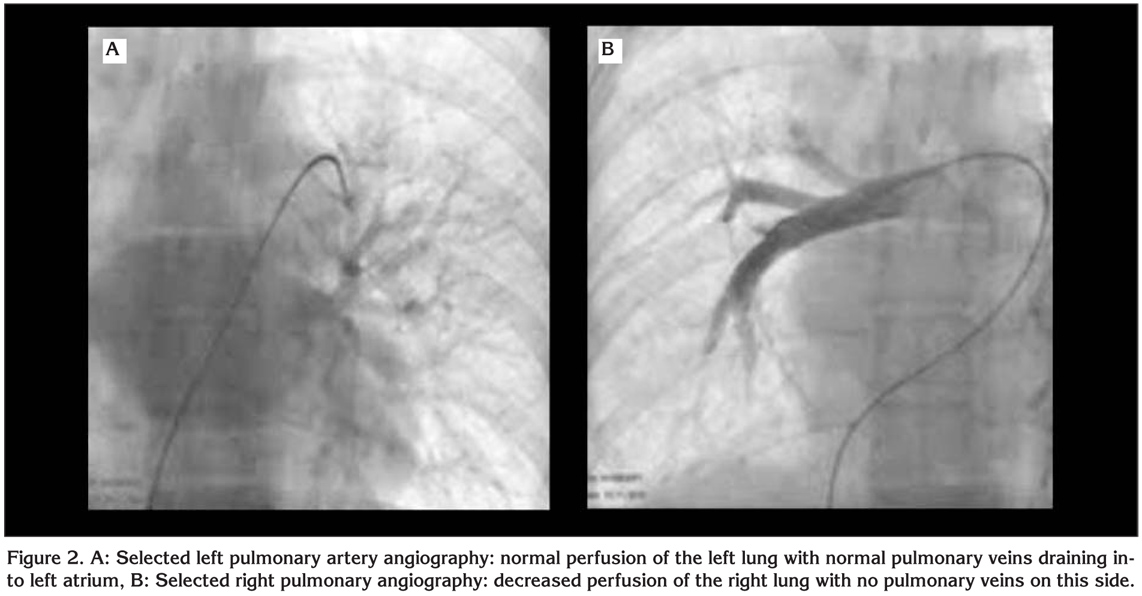

A 20-year-old female college student admitted to our clinic with dsypnea on exertion. She had this complaint for two years. On her past medical history she had pneumonia three years ago. On physical examination respiratory sounds were decreased on right hemithorax and cracles were heard on base of the right lung. Direct chest X-ray was obtained which revealed reduced volume of the right lung with shift of trachea to this side (Figure 1A). Computed tomographic examination of the chest showed decreased volume and interstitial disease pattern on right lung with shift of mediastinal structures to ipsilateral side. Right pulmonary veins were not identified on tomographic scans (Figure 1B). On transthoracic Doppler echocardiographic examination the right pulmonary veins were also could not be visualized. The estimated systolic pulmonary pressure on Doppler examination was normal. The right and left ventricular function were found as normal and interatrial and interventricular septums were intact. To confirm the diagnosis cardiac catheterization and pulmonary angiography were performed. On oxymetric study oxygen saturation was higher on right pulmonary artery than that of the left (99% vs. 89%, respectively). This finding suggested the presence of systemic arterial blood flow to pulmonary arteries on the affected side. On selected left pulmonary artery angiography the perfusion of the left lung was identified to be normal with normal pulmonary veins draining into left atrium (Figure 2A). However on selected right pulmonary angiography decreased perfusion of the right lung was noted and pulmonary veins on this side were not visualized (Figure 2B). Instead prominent intercostal arteries were identified supplying blood to the right lung. The patient was discussed with cardiologists and cardiovascular surgeons and conservative approach was chosen for her. She and her family were informed about this condition and close follow up were scheduled.

Figure 2